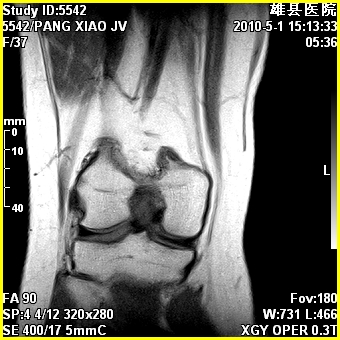

标题: MRI2894:患者右膝关节疼痛两月余,无明显外伤史 [打印本页]

标题: MRI2894:患者右膝关节疼痛两月余,无明显外伤史

右股骨下端前内侧类圆形异常信号,位于干骺端,呈长t1长t2改变,但信号不均,t1图上病灶中心见小片状稍高信号影,t2图上见散在稍低信号影,stir像呈高信号,因病灶较小,缺乏特征性改变,结合患者年龄及部位,考虑嗜酸性肉芽肿可能性大。胫骨关节面下的小囊状异常信号,如果一元论考虑则为嗜酸性肉芽肿,不过发生在这个部位的少见,二元论考虑为邻关节骨囊肿。半月板与前后交叉韧带均未见异常。

右股骨下端前内侧干骺端囊性良性病变,考虑 1内生软骨瘤 2骨囊肿 3肉芽肿。